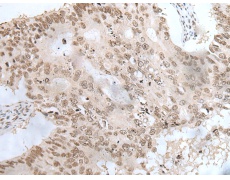

IHC positive control:

Human colorectal cancer and human ovarian cancer

IHC Recommend dilution:

20-100